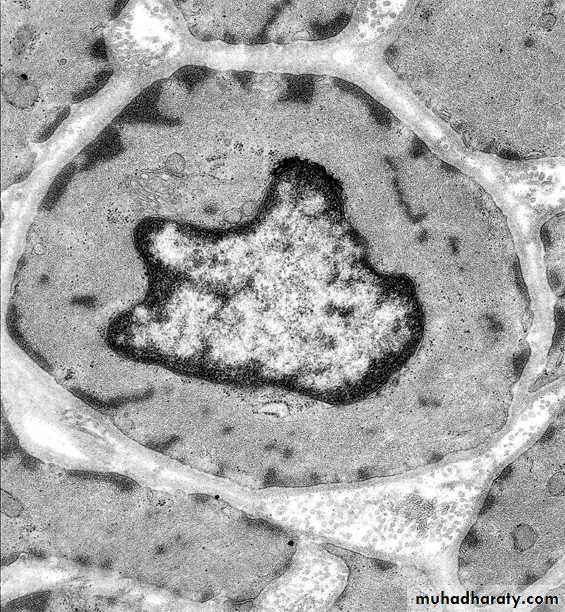

Cardiac Muscle (TEM)

Intercalated Discs Couple Heart Muscle Mechanically and Electrically

Transverse portion:

forms mechanical couplingLateral Portion:

forms electrical couplingaka “Fascia adherens”